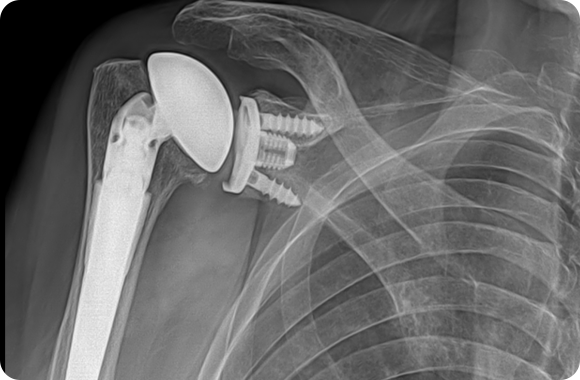

일반 어깨인공관절치환술 X-ray